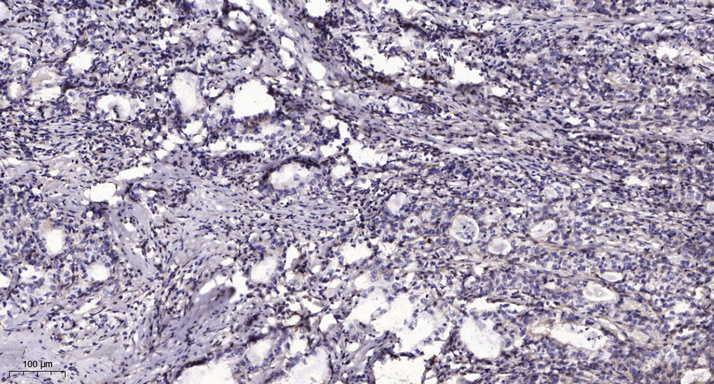

Main InformationTargetCCD19Host SpeciesRabbitReactivityHuman, MouseApplicationsIHC, IF, WBMW60kD (Observed)Conjugate/ModificationUnmodifiedDetailed InformationRecommended Dilution RatioIHC 1:50-200; WB 1:500-2000; IF 1:50-200FormulationLiquid in PBS containing 50% glycerol, 0.5% BSA and 0.02% sodium azide.SpecificityThis antibody detects endogenous levels of human CCD19PurificationThe antibody was affinity-purified from rabbit antiserum by affinity-chromatography using epitope-specific immunogen.Storage-15°C to -25°C/1 year(Do not lower than -25°C)Concentration1 mg/mlMW(Observed)60kDModificationUnmodifiedClonalityPolyclonalIsotypeIgGAntigen&Target InformationImmunogen:Synthesized peptide derived from human CCD19Specificity:This antibody detects endogenous levels of human CCD19Gene Name:CCDC19 NESG1Protein Name:CCD19Other Name:Coiled-coil domain-containing protein 19, mitochondrial ; Nasopharyngeal epithelium-specific protein 1 ;Background:tissue specificity:Expressed in nasopharyngeal epithelium and trachea but not in esophagus, stomach, large intestine, liver, cerebrum, heart, bladder, kidney, thymus, or lung.,Function:tissue specificity:Expressed in nasopharyngeal epithelium and trachea but not in esophagus, stomach, large intestine, liver, cerebrum, heart, bladder, kidney, thymus, or lung.,Cellular Localization:Cytoplasm, cytoskeleton, cilium axoneme . Cytoplasm, cytoskeleton, flagellum axoneme . Located in the proximal region of respiratory cilia. .Tissue Expression:Expressed in respiratory cells and in sperm (at protein level) (PubMed:33139725). Expressed in nasopharyngeal epithelium and trachea (PubMed:10524255).